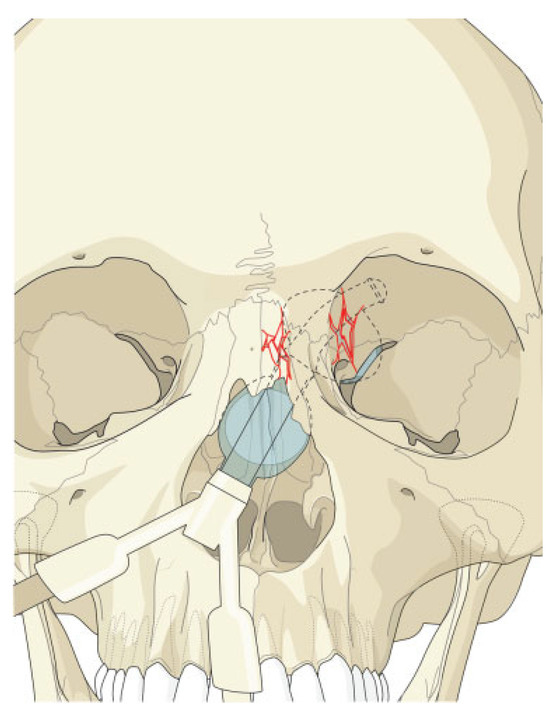

Iatrogenic Oculocardiac Reflex in a Patient with Head Injury

:Case Report